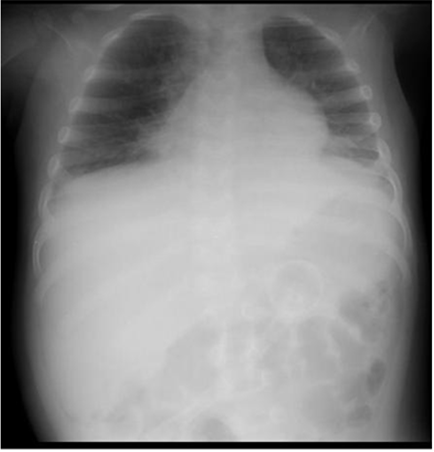

Upon admission to the emergency room, chest X-ray (X-ray) revealed veiling at the apex of the right lung and opacity in the perihilar region of both hemithorax (Figure 1A), with RT-PCR for SARS-CoV-2 being collected, with a negative result.

The patient was kept on NIV using the Bennett 840® device, with a non-ventilated full face mask, interspersed every six hours by an orofacial mask for six consecutive days. The ventilatory parameters used, as well as the SpO2 / FiO2 and PaO2 / FiO2 ratio can be seen in Table 1, as well as the chest x-ray (Figure 1B) showing improvement of the image compared to Figure 1A of the admission.